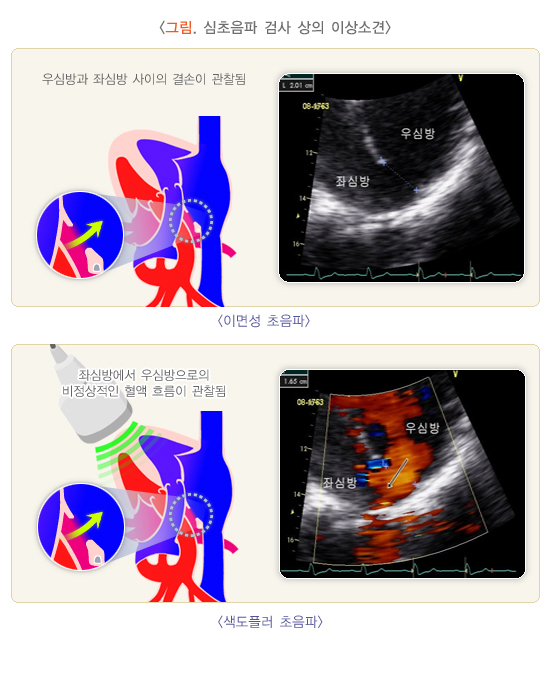

- 도플러 초음파 검사 (Duplex ultrasound)

- 하지정맥류 진단에 가장 중요하고 기본이 되는 비침습 검사입니다.

- 혈관 초음파로 혈관 구조를 확인하고 도플러를 통해 혈액의 흐름 방향, 속도, 역류 여부 및 역류 시간을 측정합니다.

- 이 검사를 통해 정맥 내 판막 손상 부위에서 혈액이 역류하는 정도를 평가하고, 정맥류의 원인이 되는 혈관을 정확히 찾아낼 수 있습니다.

- 도플러 초음파 검사 (Doppler Ultrasound)

- 일반 초음파의 원리에 도플러 효과를 적용한 검사로, 움직이는 혈액의 속도와 방향을 실시간으로 측정할 수 있습니다.

- 혈관 내 혈류의 특성을 분석해 혈류가 정상적으로 흐르는지, 역류나 협착이 있는지 평가할 수 있습니다.

- 혈관의 기능적 상태를 파악하는 데 중요한 역할을 하며, 하지정맥류, 동맥 협착, 혈전 등 혈관 질환 진단에 쓰입니다.